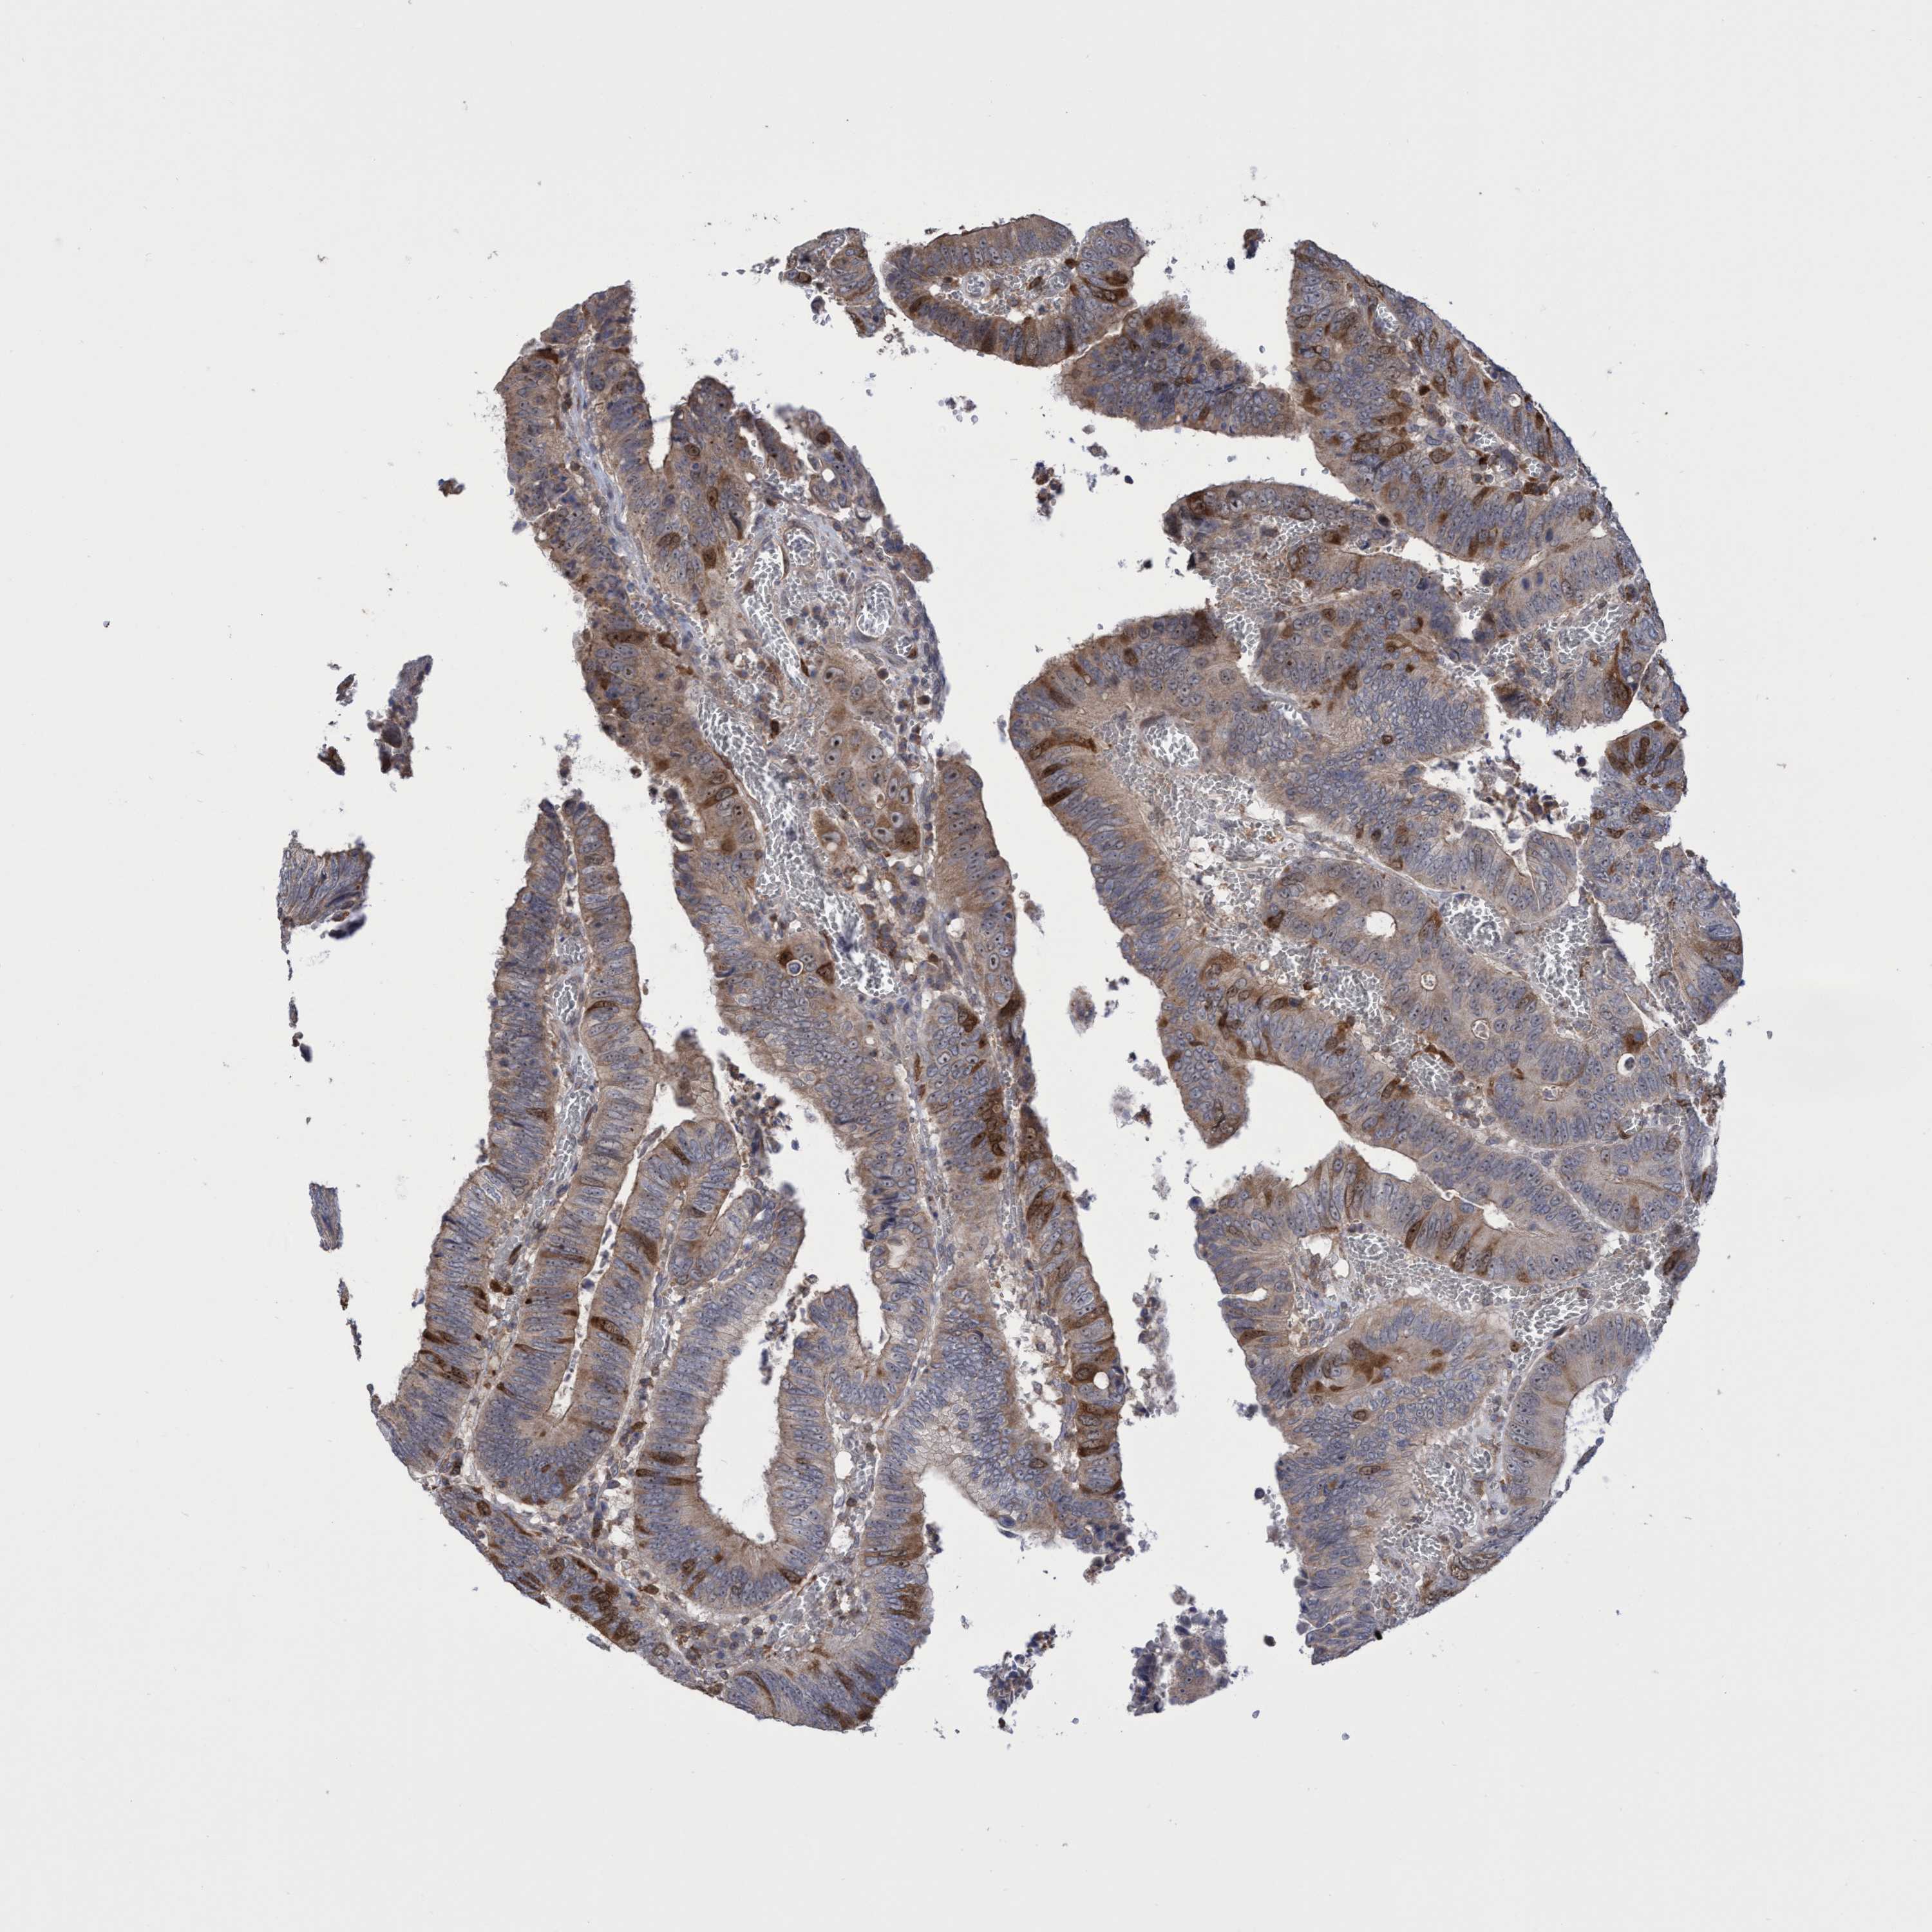

CANCER COLORECTAL CANCER Show tissue menu

Colorectal cancer

Colon adenocarcinoma